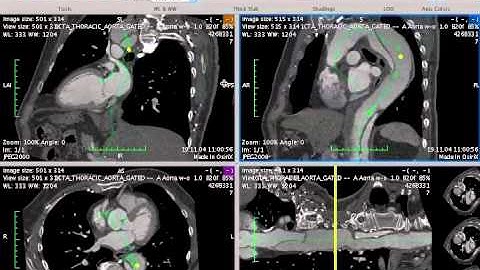

Semi-Automatic Segmentation in Osirix